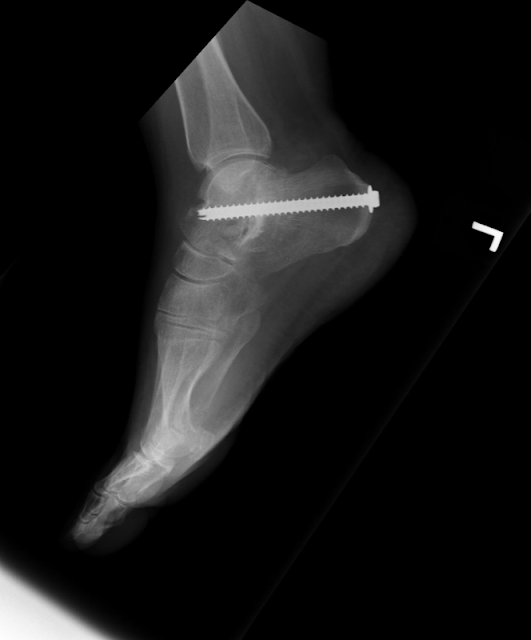

Imagens de Raio X de tornozelo/Pé

Resolvi comentar algumas imagens de Raio X que tinha no PC pra vocês. Depois comentem o que acharam...

A primeira Imagem, Mostra uma artrodese da articulação subtalar e foi realizada para estabilizar e diminuir a dor desta articulação, decorrente de um importante desgaste articular. Observa-se claramente esse desgaste Através dessa linha clara no contorno articular.

Outra causa comum para o referido procedimento é como alternativa de tratamento de seqüelas dolorosas de fraturas complexas do calcâneo. Para mais informações sobre a subtalar vale uma olhadinha no vídeo: http://www.youtube.com/watch?v=0R4zRSE_-40